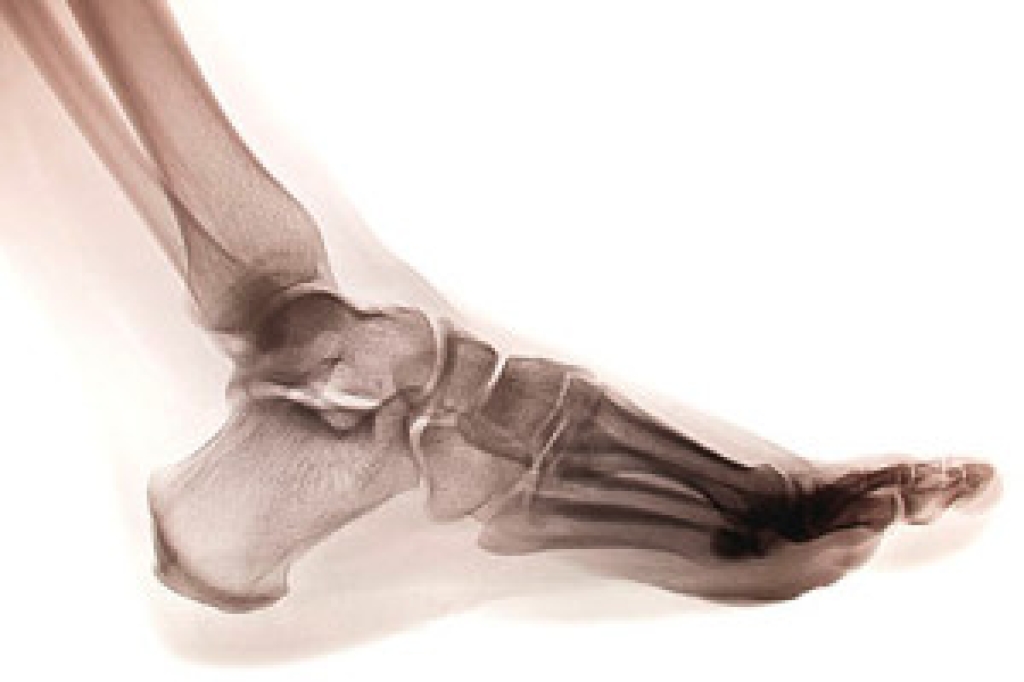

Some symptoms your child might be experiencing if they have a broken toe are swelling, redness, severe pain, and discomfort. These symptoms typically occur at the time of the injury. In more severe fractures, the bone may protrude from the skin, which is referred to as a dislocated bone. Broken toes can happen for a variety of reasons including: stubbing the toe against a piece of furniture, stepping off of a curb unexpectedly, or jamming it while participating in sporting activities. If the pain is extreme, an X-ray should be performed to determine the extent of the fracture. If your child has broken his or her toe, it is advised that you speak to a podiatrist who can discuss proper treatment options with you.

Although most people try to avoid foot trauma such as banging, stubbing, or dropping heavy objects on their feet, the unfortunate fact is that it is a common occurrence. Given the fact that toes are positioned in front of the feet, they typically sustain the brunt of such trauma. When trauma occurs to a toe, the result can be a painful break (fracture).

Severe toe fractures may be treated with a splint, cast, and in some cases, minor surgery. Due to its position and the pressure it endures with daily activity, future complications can occur if the big toe is not properly treated.